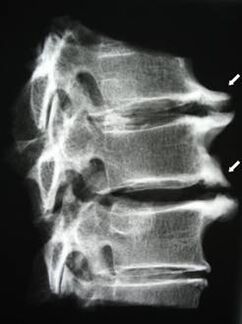

In the early stages, cartilage degeneration is detected by MRI.The pathology can then be diagnosed using x-rays.On radiography of the cervical spine, the distance between the vertebrae decreases, pathological changes in the facet joints and osteoporosis become noticeable.

| Cervical bone degeneration | The appearance of pathological changes in one or more motion segments of the spine.Impaired spinal mobility, development of myofascial pain syndrome and spinal root compression | Pain, paresthesia and movement disorders in the neck area, spreading to the back of the head and upper limbs.Detect characteristic changes in the spine on MRI and X-ray (osteoporosis, reduced distance between vertebrae, signs of damage to the intervertebral joints) |